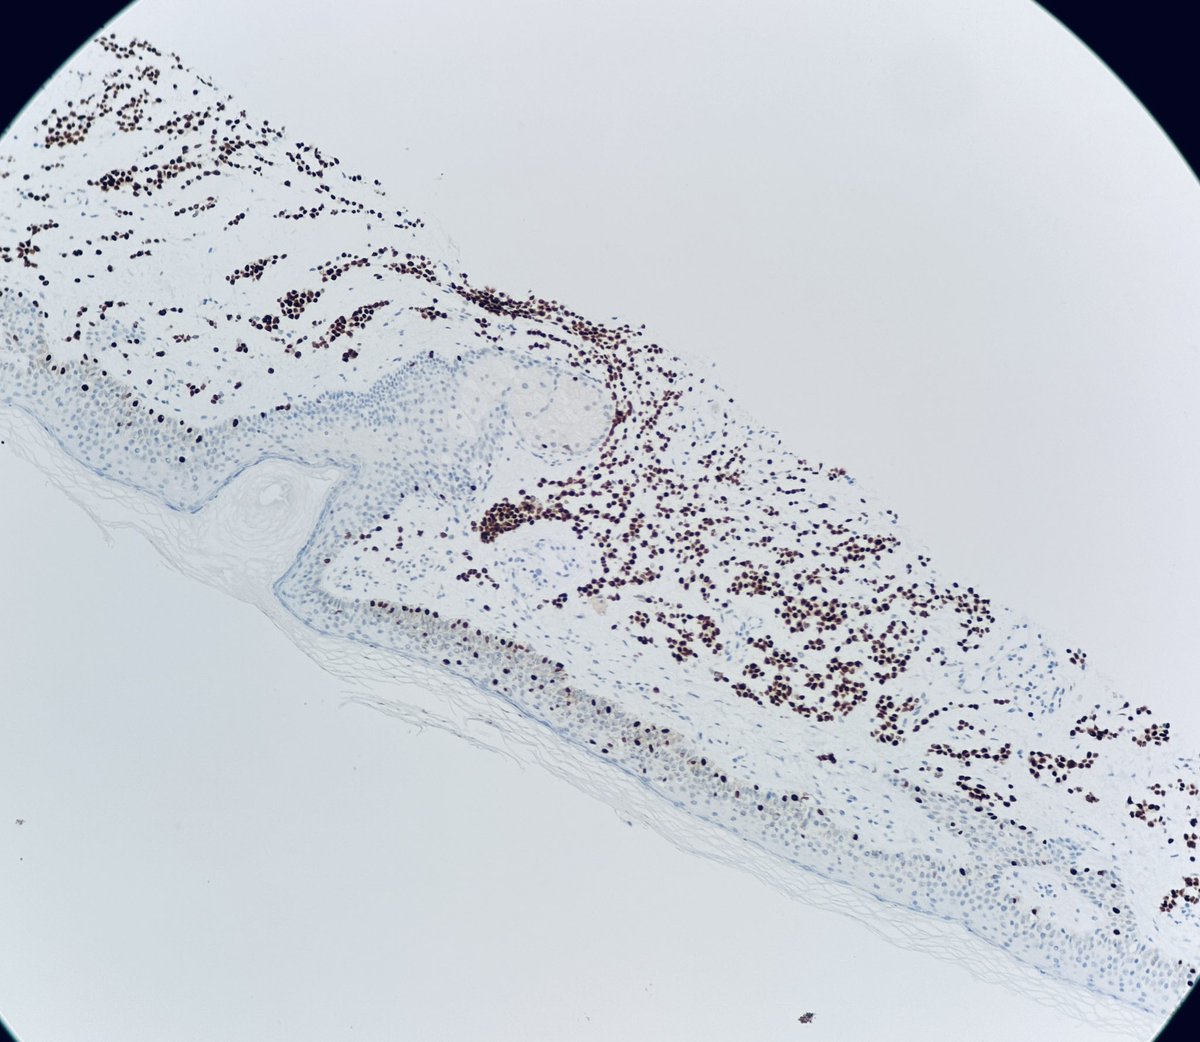

#dermpath 62 yo Man upper back. You worried about this โ€œnevusโ€ ? @david_terrano @et565 @DrGeeONE @SGottesmanMD @kis_lorand @HoustonArsenal @Dr_Jukic @glinglerimek @pembeoltulu @gonzadetoro stains are SOX10 and P16โ€ฆ